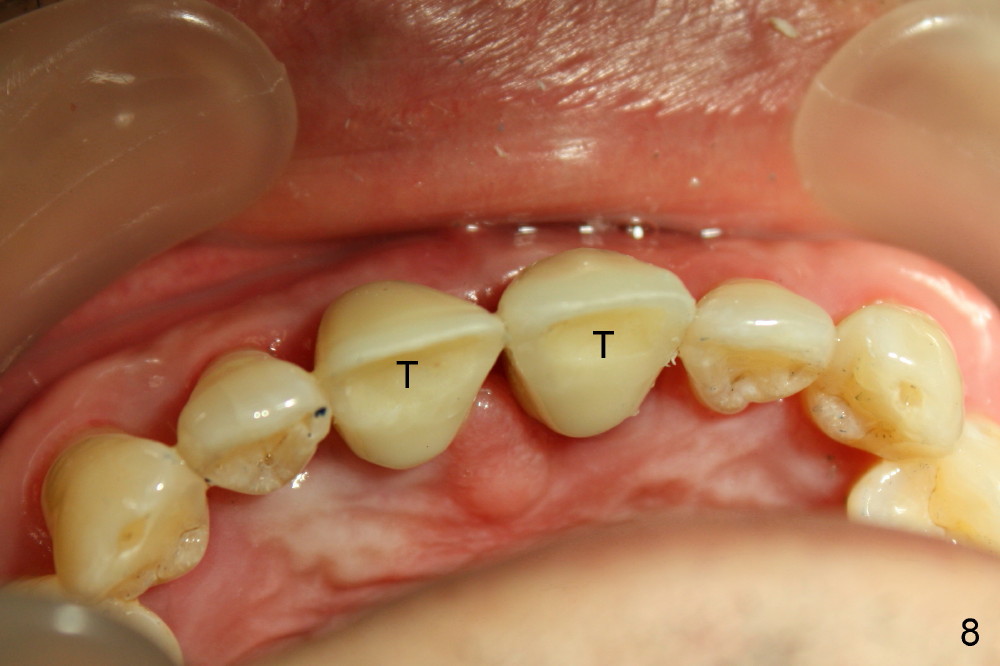

In fact two of 4.5x20 mm implants are placed immediately following extraction. Insertion torque is greater than 60 Ncm, partially because of apparent engagement of the implants into the nasal floor (cortical bone; Fig.9). Following placement of 3.5x5 mm abutments, immediate provisionals are fabricated (Fig.7,8).

Definitive restoratons (Zirconium crowns) are seated (Fig.15,16). There is no sign of infection. The patient is pleased. In fact the nasal floor does not seem to have been lifted by the implants, as revealed by CT taken 5 years post cementation (Fig.17,18).